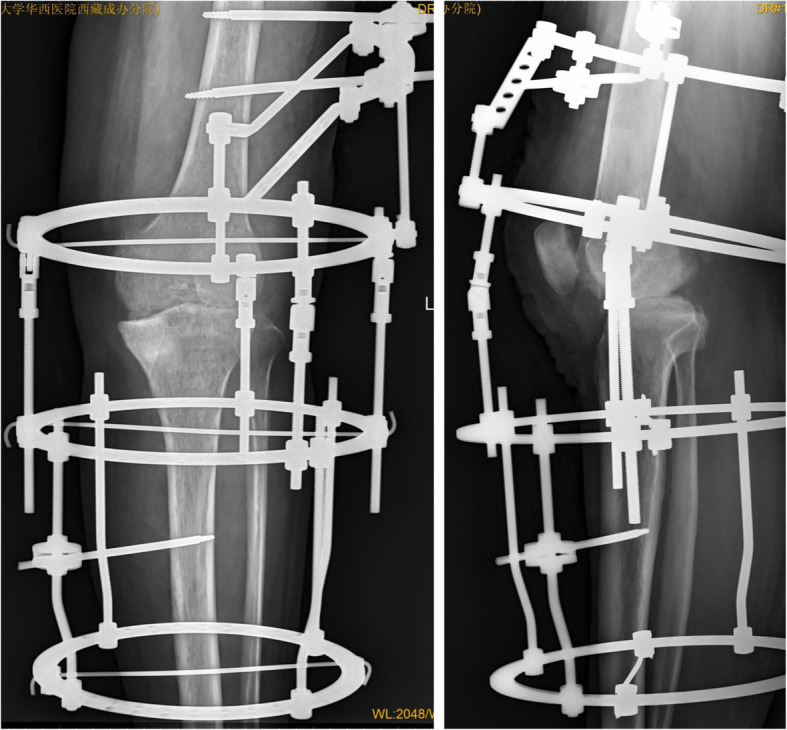

Fig. 4.

X-ray (anteroposterior and lateral): good bony contact after operation

The ESR and CRP concentrations for all 24 patients returned to normal within 5.1 months (2–6 months) postoperatively. There was no reported recurrence of TB postoperatively. Radiographic images after removal of the external fixator revealed that the mean leg-length discrepancy was 2.7 cm (0.8–4.9 cm) after fusion, and the mean postoperative alignment was 8.7° flexion (5–15°) and 5.3° valgus (5–10°) (Figs. 6, 7 and 8). No patient had a significant rotational deformity. The mean Lysholm score improved significantly from 36.8 (28.0–49.0) preoperatively to 79.5 (65–86) at the final follow-up (p < 0.0001).

Fig. 6.

X-ray (anteroposterior and lateral): good knee fusion after removal of the external fixator (8.5 months after surgery)